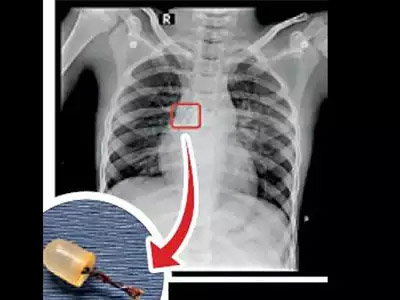

ଫରିଦାବାଦ୍,୭।୨: ହରିୟାଣାର ଫରିଦାବାଦରେ ଏକ ଅଭାବନୀୟ ଘଟଣା ଘଟିଛି। ଜଣେ ୧୦ ବର୍ଷୀୟ ବାଳକଙ୍କ ପେଟରୁ ଏଲ୍ଇଡି ବଲ୍ ବାହାର କରାଯାଇଛି। ଫରିଦାବାଦର ସେକ୍ଟର ୬୨ରେ ରହୁଥିବା ପ୍ରମୋଦ କୁମାରଙ୍କ ଭଣଜା ଅଭିଷେକ(୧୦) ୧୦ ଦିନ ପୂର୍ବେ ଖେଳୁଥିବାବେଳେ ପ୍ରବଳ କାଶ ହୋଇଥିଲା। ଏହାପରେ ଛାତିରେ ଯନ୍ତ୍ରଣା ମଧ୍ୟ ହୋଇଥିଲା। ତାଙ୍କୁ ପରିବାର ଲୋକେ କାଶ ଔଷଧ ଆଣି ଦେଇଥିଲେ। କିନ୍ତୁ କାଶ ଏବଂ ଛାତି ଯନ୍ତ୍ରଣା କମି ନ ଥିଲା। ତାଙ୍କୁ ହସ୍ପିଟାଲ ନିଆଯାଇଥିଲା। ପରୀକ୍ଷା ପରେ ତାଙ୍କ ଶ୍ୱାସନଳୀରେ କୌଣସି ଏକ ଜିନିଷ ଅଟକି ଯାଇଥିବା ଡାକ୍ତରମାନେ କହିଥିଲେ। ଅଭିଷେକଙ୍କ ବୟସ କମ୍ ହୋଇଥିବାରୁ ପେଟରେ ଅପରେଶନ କରାଯିବା ନିରାପଦ ନୁହେଁ ଭାବି ଡାକ୍ତରମାନେ ଆଧୁନିକ ଉପାୟରେ ଶ୍ୱାସନଳୀରେ ଅଟକି ଯାଇଥିବା ଜିନିଷଟିକୁ ବାହାର କରିଥିଲେ। ପରେ ଜଣାପଡିଥିଲା ଉକ୍ତ ଜିନିଷଟି ଖେଳନାରେ ବ୍ୟବହୃତ ହେଉଥିବା ଏଲ୍ଇଡି ବଲ୍ବ। ଖେଳୁଥିବାବେଳେ ଅଭିଷେକ ତାକୁ ଗିଳିଦେଇଥିବା କୁହାଯାଉଛି।